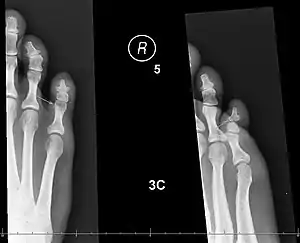

| X-rays of fractures of the proximal (left) and distal (right) phalanges in the little toe. | |